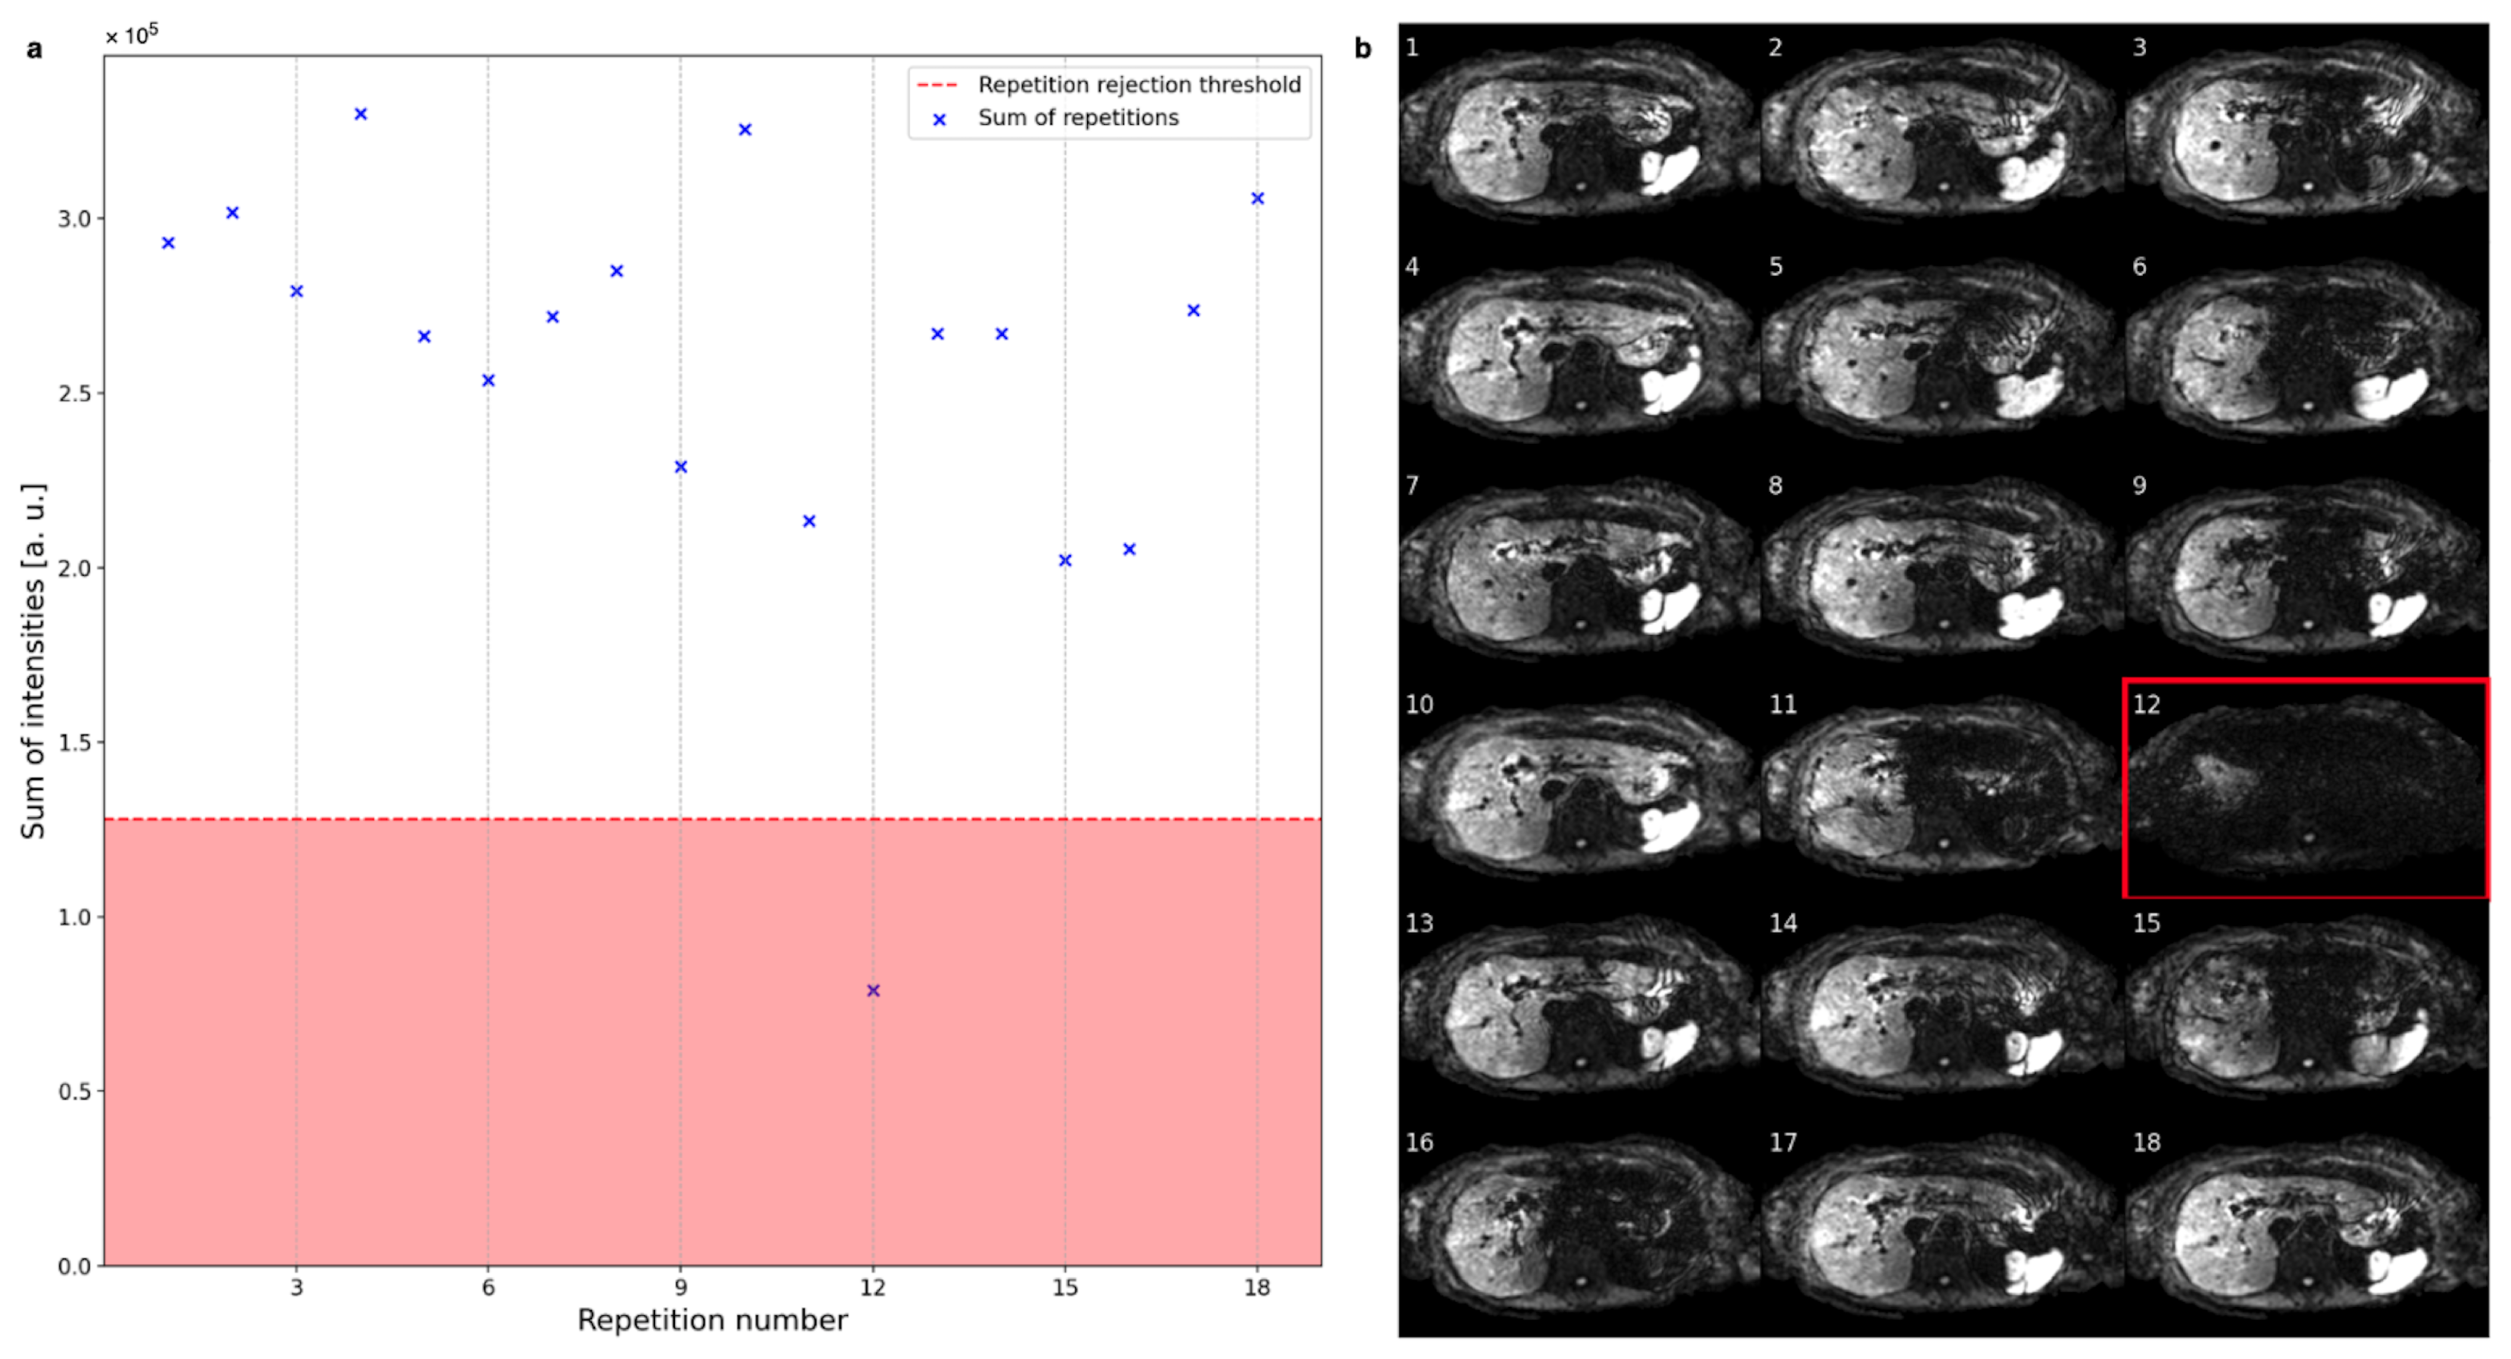

3.1. Repetition and Voxel Rejection